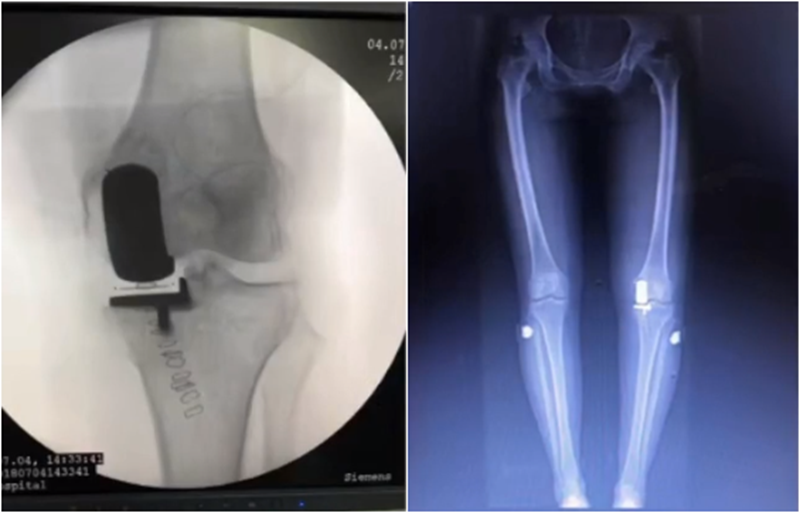

五、关于力线与假体位置——是否要求全长片?

牛津单髁课程表明,单髁只纠正关节内畸形,恢复下肢得病前的力线,不纠正关节外畸形。

但实际术后需要通过全长片来判断是否能取得好的力线,判断有无过度矫正或矫正不足的情况出现。还需要通过全长片区分内翻畸形的来源在哪里,是否能矫正,对适应证的选择有一定帮助。如果术后下肢整体力线外翻3°,则说明外侧间室压力明显升高。

小结:对于下肢整体力线,首先保证术后力线不能外翻,术后力线内翻不能超过10°,而术前关节外畸形不能超过10°。

除了下肢整体力线,还要考虑假体位置。理想状态下,假体位置对位好,力线轻度内翻。

牛津单髁在假体评判中,提到股骨内外翻有10°容忍度,胫骨内外翻有5°,股骨屈伸在0-15°之间,胫骨后倾在 7-(﹣5)后倾之间。但评判标准中没有提到此种方式是基于全长片还是局部片。

文献中建议假体内外翻不大于4°,如果假体出现外翻,后倾大,会造成内侧皮质压力异常增高,增加内髁骨折风险。如果假体内翻超过5°,增加胫骨平台松动风险。

但有时候力线好,假体和外侧关节线会成角,那么对于此种情况,应如何判断假体位置内外翻定义?和外侧关节线比较,属于外翻假体;和下肢机械轴比较,属于中立位假体。

小结:判断股骨胫骨假体位置,是基于局部X线的判断,是考虑行走时关节线的方向为基准,此时内外翻不能超过5°,而不能从全长片来判断。